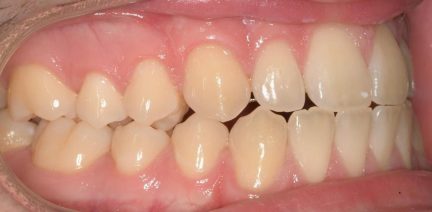

État initial

Classe III, articulé croisé postérieur, articulé croisé antérieur, occlusion bout-à-bout, articulation ouverte, arcades étroites, arcades asymétriques, déviation médiane maxillaire, déviation médiane mandibulaire, décalage médian, chevauchement, rotations

- Relation de classe I obtenue

- Articulé antérieur corrigé

- Articulé postérieur corrigé

- Surplomb et recouvrement normaux obtenus

- Lignes médianes coïncidentes